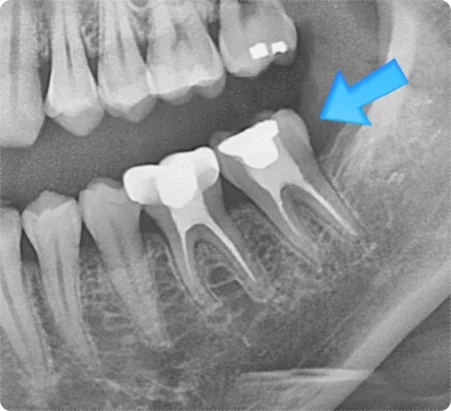

신경치료는 치아 내부 신경을 제거하고 치료하기 위해 구멍을 뚫어 접근하는 과정입니다.

이 과정에서 치아는 본래보다 약해질 수밖에 없고, 그대로 두면 쉽게 깨지거나 손상될 수 있습니다.

* 신경치료만 진행 → 약해진 치아, 균열/파절 위험 증가

* 신경치료 + 크라운 치료 → 치아 구조 보강, 장기적 사용 가능